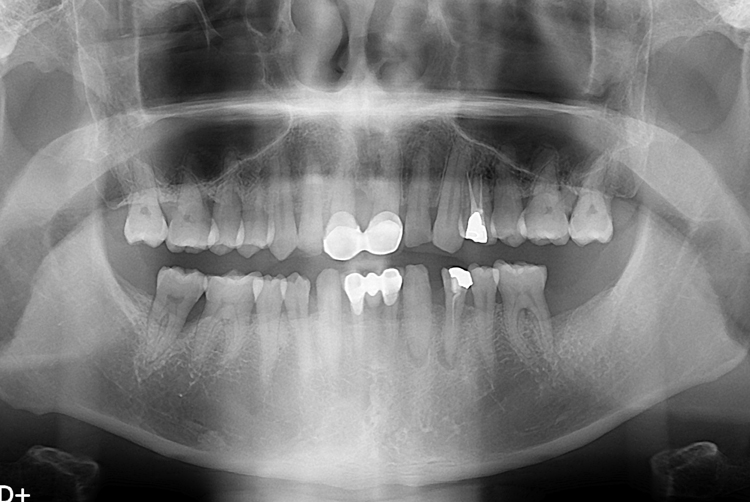

[임플란트] 어금니 임플란트

치료후 : 2017-04-03

세종치과는 많은 환자와 다양한 케이스를 바탕으로

항상 편안한 임플란트 수술을 제공하고자 노력하고,

오래동안 튼튼히 쓸 수 있는 임플란트 수술을 가장 큰 목표로 삼고 있습니다.